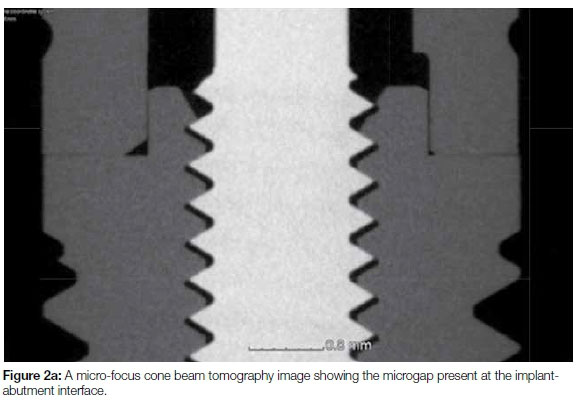

Proposed criteria of acceptable bone loss of 1.5 mm during the first year of loading, and 0.2 mm annually thereafter, are still widely accepted by the scientific community.16 Significant changes in implant treatment protocols have occurred, ranging from using machined-surfaced implants and mainly restoring the edentulous jaw, to current protocols involving surface-enhanced implants restoring single missing teeth. Many other non-infectious factors may also contribute to early bone loss. The reader is referred to a published article for a more comprehensive review on this topic.25 The amount of bone remodeling depends on implant hardware, surgical technique, prosthesis design, and patient factors.16,25 The presence or absence of a dental implant-abutment interface that may harbor bacteria plays an important role in peri-implant health. A chronic presence of inflammatory-cell infiltrate is found whenever a micro-gap is present (Figures 2a and 2b).20 Histological differences exist between periodontitis- and peri-implantitis lesions.